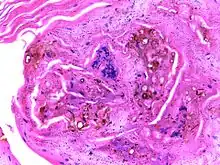

| Micrograph of chromoblastomycosis showing sclerotic bodies | |

The most informative test is to scrape the lesion and add potassium hydroxide (KOH), then examine it under a microscope. (KOH scrapings are commonly used to examine fungal infections.) The pathognomonic finding is observing medlar bodies (also called muriform bodies or sclerotic cells). Scrapings from the lesion can also be cultured to identify the organism involved. Blood tests and imaging studies are not commonly used. On histology, chromoblastomycosis manifests as pigmented yeasts resembling "copper pennies". Special stains, such as periodic acid Schiff and Gömöri methenamine silver, can be used to demonstrate the fungal organisms if needed.